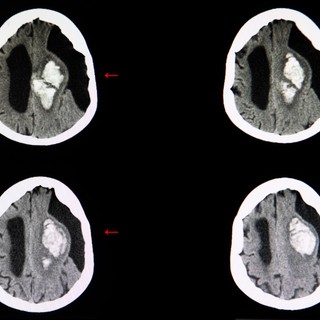

A kis ciszták általában nem okoznak tüneteket és csak véletlenül kerülnek felfedezésre. A tünetek során felmerülő gyanú esetén MR (mágneses rezonancia) képalkotó vizsgálattal lehet a subarachnoideális ciszta meglétét igazolni.

Mivel a subarachnoideális ciszták megjelenése képalkotón több más struktúrára hasonlíthat, fontos a gondos radiológiai értékelés. Gyakran összetéveszthetők lehetnek tágult agykamrákkal, agyi atrófiával járó liquor-térfogat növekedéssel, vagy akár más folyadékkal telt elváltozásokkal, például epidermoid vagy dermoid cisztákkal. A korszerű MR-vizsgálat azonban kiválóan alkalmas a pontos meghatározásra: a ciszta jelintenzitása az agy-gerincvelői folyadékkal megegyező, a falai vékonyak, és érdemi kontrasztanyag-halmozást nem mutatnak.